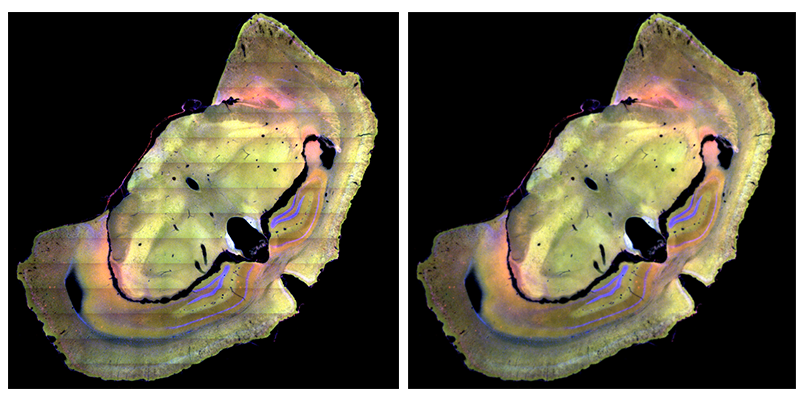

超大尺寸病理切片的全景获取技术

基于超大尺寸病理切片的全景获取技术,TissueFAXS系统可以支撑大数据高通量影像学数据分析,为珍贵大样本数字化拷贝建库以及多学科交叉研究获取更高丰度的数据提供研究条件。

通过这种全景成像分析获得的数据,避免了因传统小视野区域分析造成的不确定性,保证了在同一分析参数下,不同研究者对相同样本获得的分析数据的一致性。自动化组织全景扫描及分析;多聚焦保证采集图像清晰、完整;动态聚焦/ 景深扩展/ Z-stack成像/2.5x-100x全景成像。

左起:新生鼠全切片(1X标准玻片);食蟹猴全脑样本(2X玻片);深海鱼头部样本(4X玻片);虎鲸脑叶样本(8X玻片)